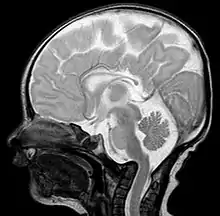

Basilar invagination is invagination (infolding) of the base of the skull that occurs when the top of the C2 vertebra migrates upward. It can cause narrowing of the foramen magnum (the opening in the skull where the spinal cord passes through to the brain). It also may press on the lower brainstem.[1]

- Magnetic resonance imaging (MRI), which usually provides the most information